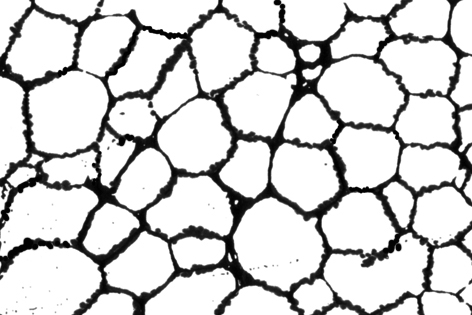

■ hypocellular marrowの細胞分布パターン

細胞存在パターン;左:hypo-diffuse 右:hypo-patchy

Hypo-diffuseは存在すれば「病気」の異常な状態とみなしてよい。Hypo-patchyは高齢者骨髄に似る所見